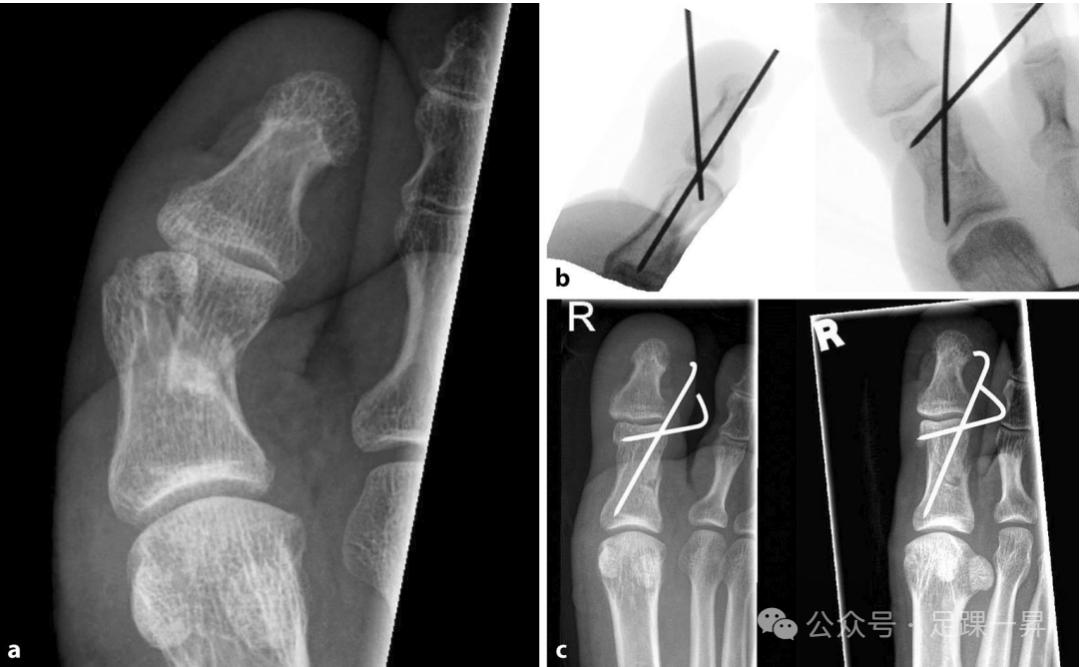

▲图示**趾近端趾骨粉碎性骨折。通过闭合复位撬拨技术联合经皮克氏针固定进行手术治疗。a 术前X线片;b 术中影像学检查;c 术后2周X线随访检查。